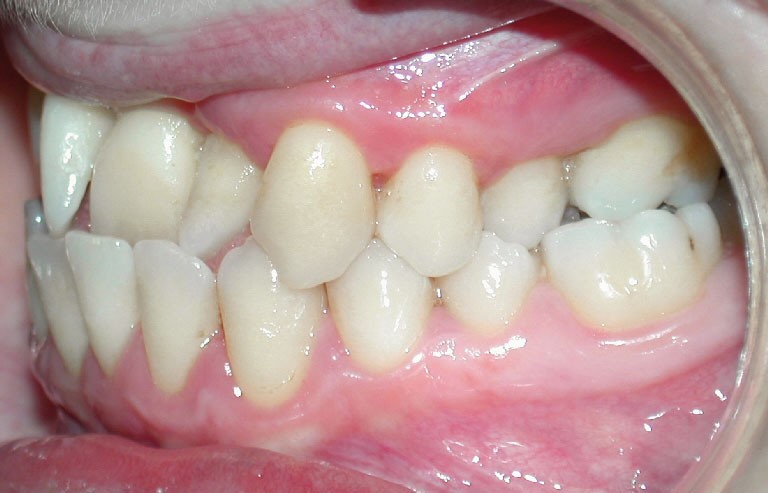

Cette patiente est venue consulter pour son occlusion inversée et ses importantes malpositions dentaires antérieures associées à la perte d’une dent et à des problèmes parodontaux.

• Malocclusion de classe III d’Angle par rétroalvéolie maxillaire,

• endoalvéolie maxillaire avec occlusion inversée antérieure et bilatérale,

• infraclusion incisive,

• fortes malpositions des incisives supérieures (dont 22 qui est en rotation axiale disto-palatine de 90°), • dysharmonie dento-dentaire (12 en « grain de riz » est aussi en rotation marginale disto-palatine de 45°),

Le sourire est inesthétique (fig. 3) et de profil il existe une rétrochéilie supérieure (fig. 2).